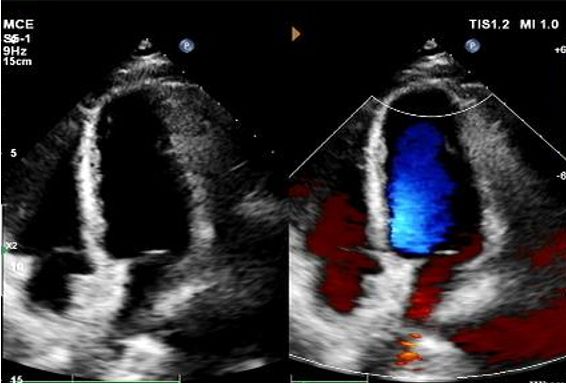

Echo 1-letnie:

No visible disc structures – replaced by 8mm tissue thickening at the septal implant site.

Zero residual shunt (rest or post-Valsalva).

Potwierdzono pełną absorpcję urządzenia.